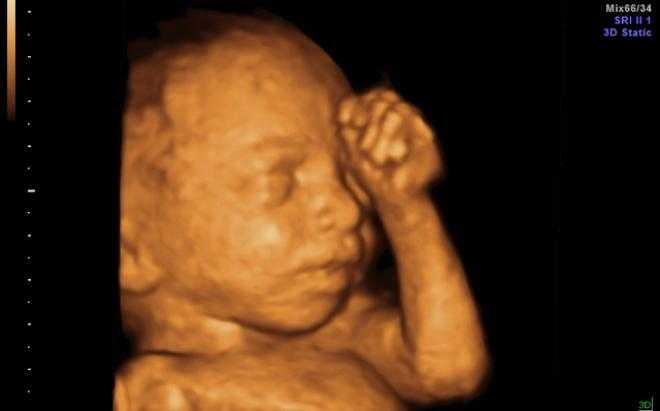

3D

Поможет увидеть объемное изображение с 3D визуализацией, на мониторе будет отображаться трехмерная картинка, что позволит хорошо рассмотреть плод. Назначается с 20 по 33 неделю беременности, когда сформировались внутренние органы ребенка. Длится обследование 45 минут, позволяет определить наличие патологий, рассмотреть плод независимо от его положения.